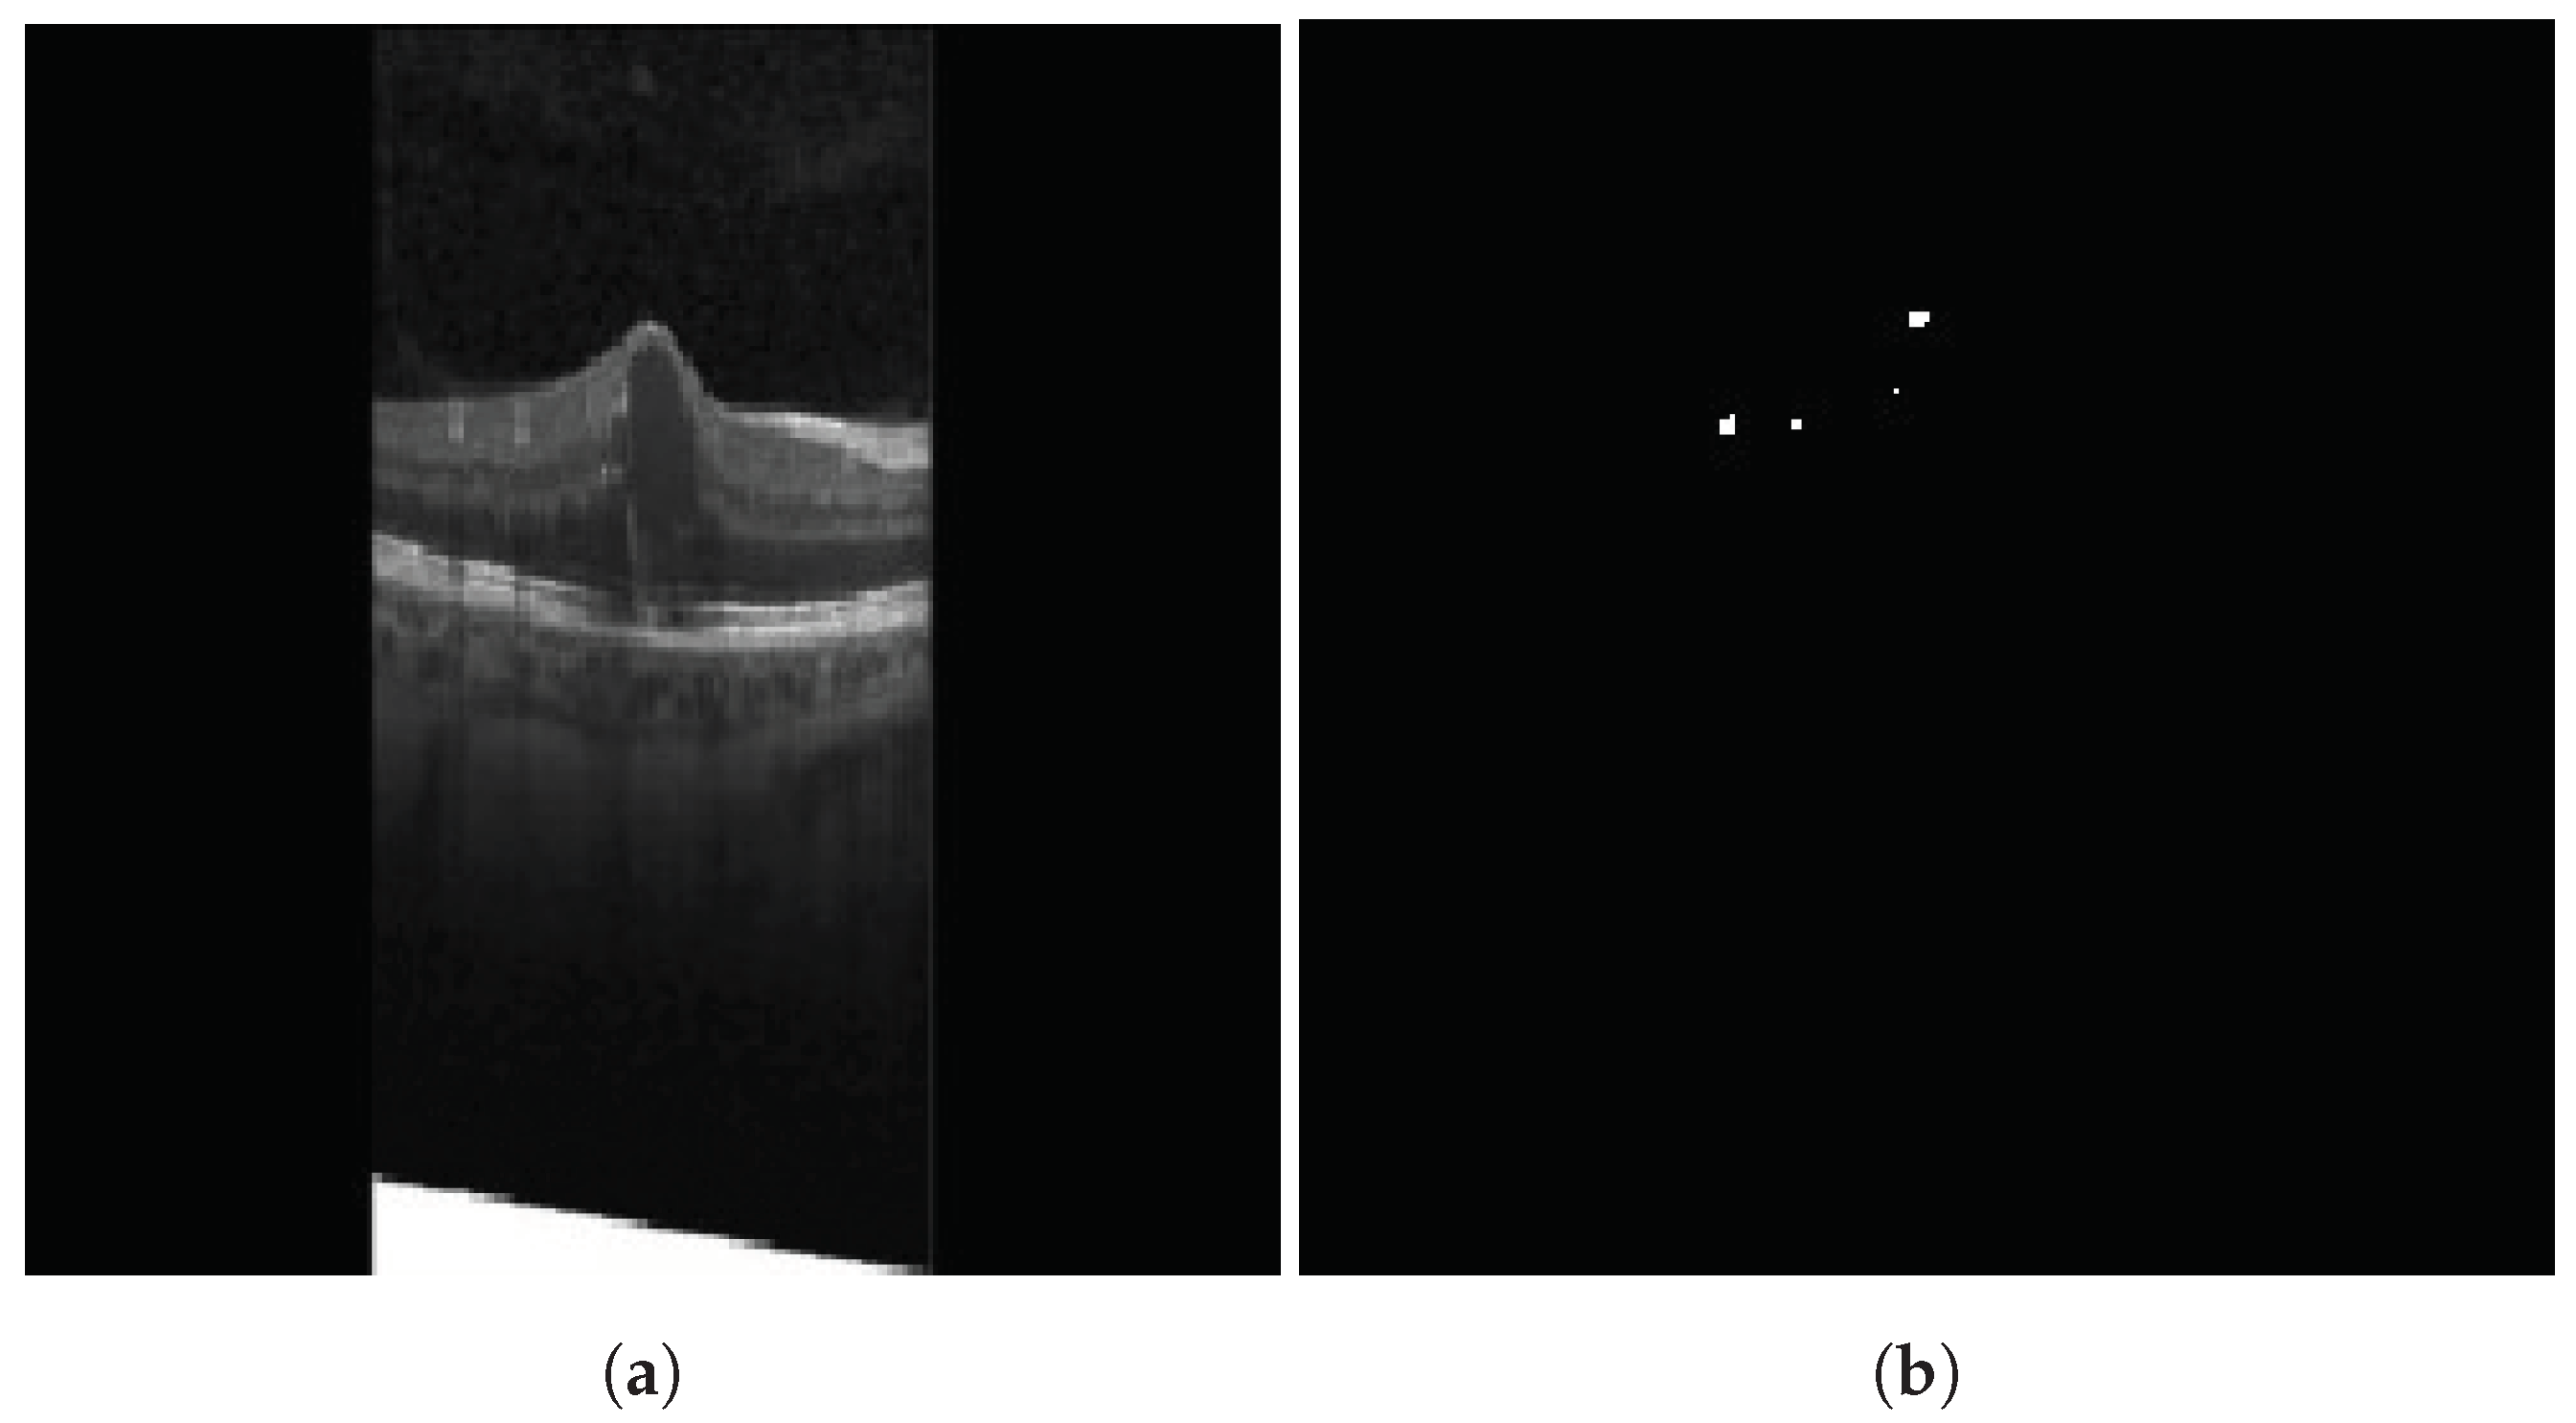

3.1.2. Hyperreflective Focii (HRF)

4.3.3. Cystoids